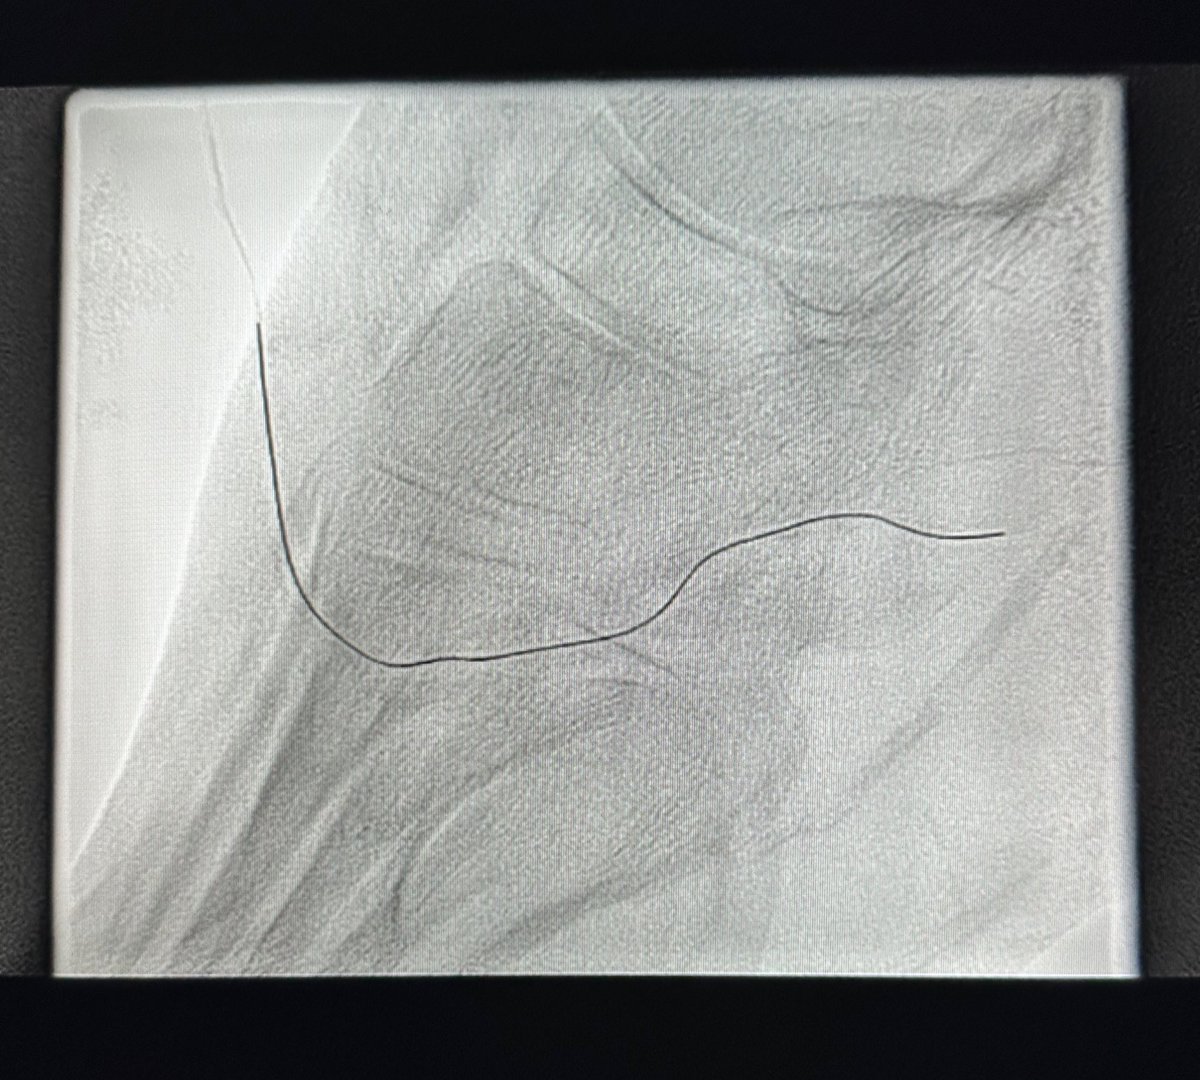

ابداع من أخصائية الأشعة @itskhulud_ في توضيح ما نراه بالأشعة التداخلية اثناء علاج دوالي الخصية العائدة بعد الجراحة حيث يتم ربط القليل من الاوردة الكبيرة وترك الباقي. احدث التقنيات والتطورات الطبية متوفرة في جامعة الملك سعود @ksumedicalcity

Naif Alsaikhan | د. نايف بن حمد الصيخان tweet mediaNaif Alsaikhan | د. نايف بن حمد الصيخان tweet media